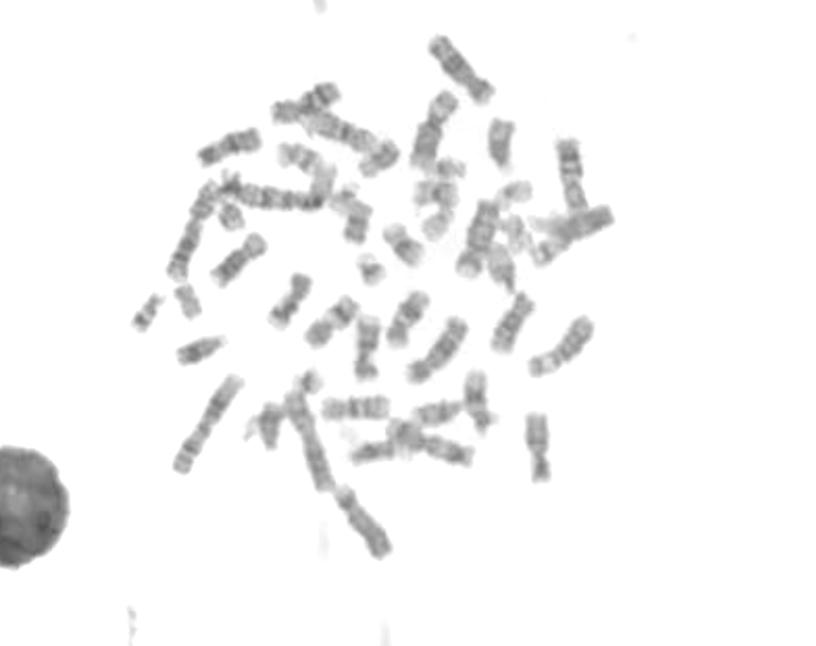

Karyotyping

Automated metaphase detection for genetic testing and cytogenetic studies for high-accuracy pattern recognition